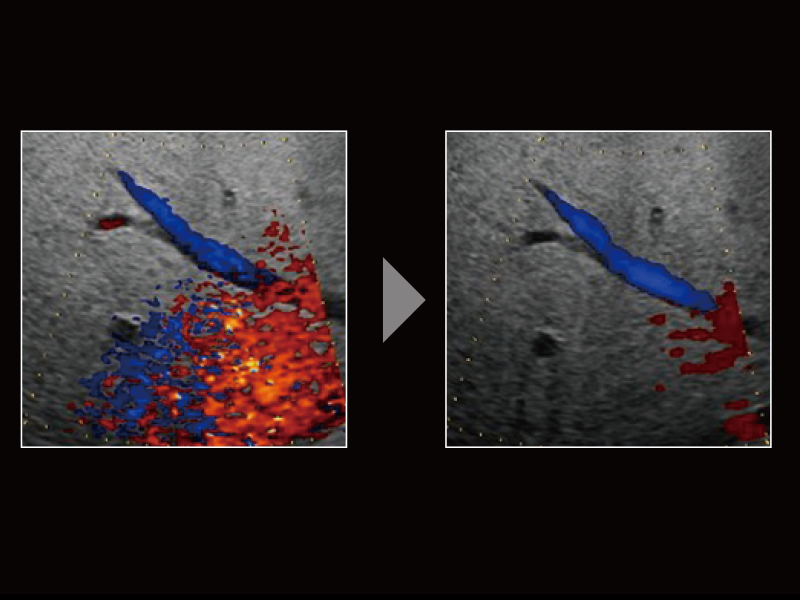

~血流感度と体動ノイズ抑制とのバランスを実現~

微細血流を表示する技術であるDetective Flow Imaging(DFI)は、ノイズ処理技術 “Wall Motion Reduction PLUS” を加えることで、ノイズを選択的に抑制し、感度と視認性の高い画像を実現しました。 “Wall Motion Reduction PLUS” は、検出した信号強度のばらつきを判定することで、各部位の体動量に応じたノイズ低減を行います。

~フィルタ処理の改善と信号速度のばらつき判定による感度向上を実現~

ウォールフィルタをより低速側にシフトすることで、血流感度の向上を実現しました。フィルタ処理の変更によって生じる体動ノイズに対し、複数回の受信によって検出した信号速度のばらつきを判定することで効果的にノイズの低減を行います。